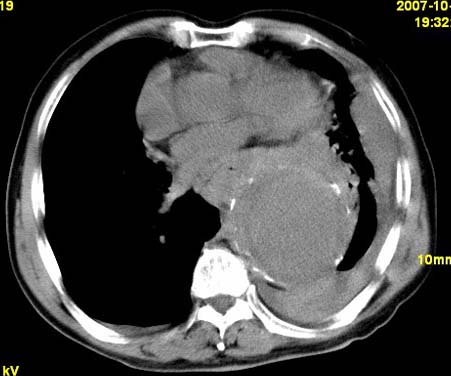

标题: CT10190:男,70,胸部疼痛数年,加重一天。典型病例。 [打印本页]

标题: CT10190:男,70,胸部疼痛数年,加重一天。典型病例。

典型降主动脉瘤伴血栓形成.瘤体下部局部边缘不清,结合病史,不除外局部撕裂外渗可能.另左侧胸水,肺部压迫不张改变.建议增强进一步检查.

胸主动脉瘤附壁血栓形成并破裂出血

1.降主动脉瘤伴血栓形成.2.左侧胸腔积液,考虑为主动脉瘤破裂所致

降主动脉明显增粗,边缘模糊,周围低密度影,双侧胸膜腔少量积液,结合临床考虑胸主动脉瘤破裂并双侧胸腔积液。